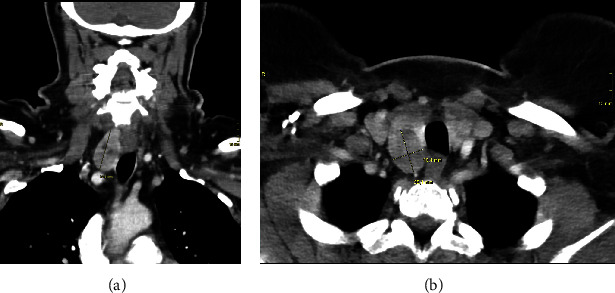

Background: The co-occurrence of medullary thyroid carcinoma (MTC) and papillary thyroid carcinoma (PTC) is thought to be a rare phenomenon. Here, we present a patient undergoing surgery due to a suspected MTC. Histopathological workup confirmed the suspected diagnosis but also described an incidental PTC in the contralateral lobe with lymph node metastasis in the central cervical compartment. Case Presentation: A 58-year-old female presented with thyroid nodules and significantly elevated levels of calcitonin and carcinoembryonic antigen (CEA). She underwent total thyroidectomy along with central and bilateral lymph node dissection. Histology revealed a MTC of 20 mm and a BRAF V600E-positive PTC of 11 mm with central cervical lymph node metastasis. Postoperatively, ablative radioiodine therapy was performed. Two months later, both calcitonin and CEA were normalized. Conclusion: Simultaneous occurrence of MTC and PTC seems to be rare, but recent literature suggests that simultaneous occurrence is probably more frequent than initially thought. Preoperative calcitonin can be helpful in the diagnostic workup of thyroid nodules. Due to different treatment strategies, precise histological differentiation of potential lymph node metastasis is essential.